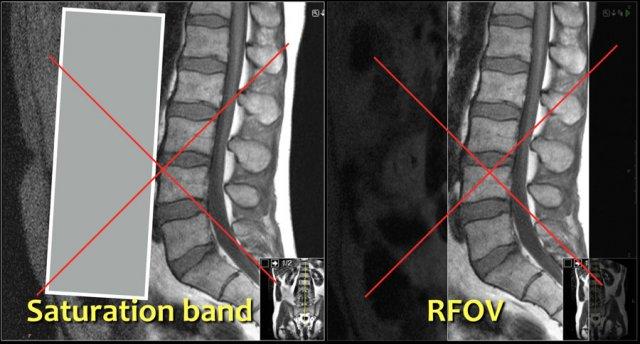

Không sử dụng dải bão hòa ở phía trước hoặc trường nhìn hình chữ nhật (RFOV), vì cần khảo sát cả phần mô mềm trước cột sống.

Đặc biệt cần chú ý tìm kiếm phình động mạch chủ bụng, vì đây cũng có thể là nguyên nhân gây đau thắt lưng.

Hướng mã hóa tần số nên đặt theo chiều trước-sau (AP) và do đó hướng mã hóa pha sẽ theo chiều chân-đầu.

Cách thiết lập này có một số ưu điểm:

- Độ phân giải cao nhất theo hướng mã hóa tần số.

Chúng ta cần độ phân giải cao nhất theo chiều trước-sau để phát hiện các thoát vị nhỏ và xác định rõ ranh giới các rễ thần kinh. - Khi đặt mã hóa pha theo chiều trước-sau, sẽ xuất hiện xảo ảnh do chuyển động hô hấp. Đó là lý do một số người sử dụng dải bão hòa hoặc RFOV.

Khi đặt mã hóa tần số theo chiều trước-sau, các vấn đề này sẽ không xảy ra và không cần sử dụng dải bão hòa. - Mã hóa tần số theo chiều chân-đầu có thể dẫn đến hiển thị kém các mâm đốt sống do xảo ảnh dịch chuyển hóa học tại vị trí tiếp giáp giữa mỡ trong thân đốt sống và nước trong đĩa đệm.

Đây là lý do thêm để sử dụng mã hóa pha theo chiều chân-đầu và mã hóa tần số theo chiều trước-sau.